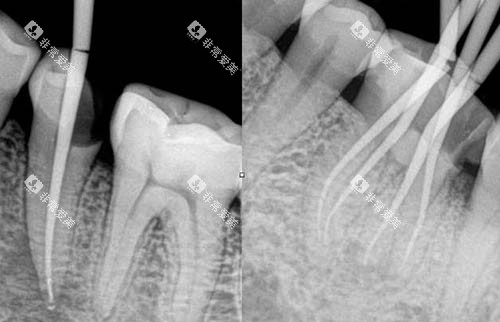

根管治疗的过程

根管治疗是治疗牙髓炎、根尖周炎等牙髓疾病的有效方法。

它主要包括根管预备、根管消毒和根管充填三个步骤。

医生会先去除感染的牙髓组织,然后对根管进行清理、消毒,然后用充填材料将根管填满。

自贡根管治疗价格

在自贡,根管治疗的价格与牙齿的部位有关。

前牙的根管治疗相对简单,费用一般在300 - 500元左右;前磨牙的根管治疗费用大约在500 - 800元;磨牙的根管治疗较为复杂,价格在800 - 1500元之间。